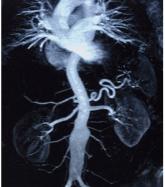

ArticleHemodynamically, the kidney is at the heart of cardiorenal syndromeAuthor:Justin L. Grodin, MD, MPHPublish date: March 1, 2018In heart failure, the heart and the kidneys share a rocky relationship.Read More